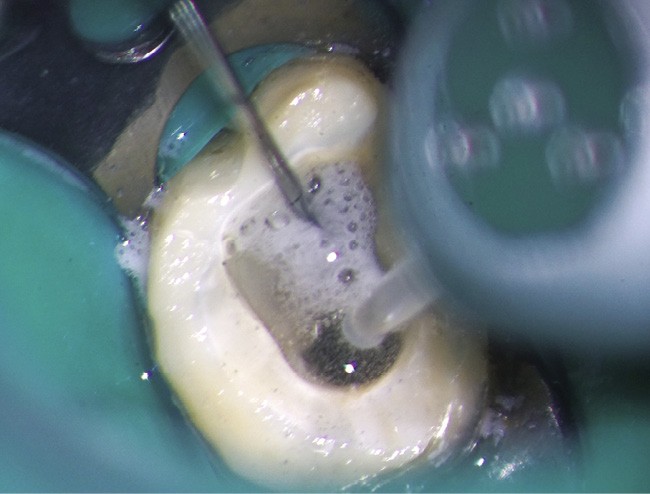

Le laser Er:YAG va permettre une élimination des débris en surface, une stérilisation, avec comme irrigation de l’eau stérile [36] et en coupant le spray, une hémostase avec la formation d’une couche de coagulation [37] propre à la formation d’un pont dentinaire au contact du biomatériau, qui peut être bio-actif, tel que la Biodentine (Septodont) (fig. 6a à d).

Protocole opératoire : sous anesthésie, une cavité suffisante à recevoir le biomatériau (2 à 3 mm) sous champ opératoire est réalisée. La désinfection au laser Er:YAG (40 mJ ; 20 Hz) sous spray, pendant 20 secondes, est alors mise en œuvre. S’en suit éventuellement une coagulation de 3 secondes, en coupant le spray, puis la mise en place du biomatériau Biodentine (Septodont). Il sera ensuite recouvert d’un matériau de restauration adéquate.